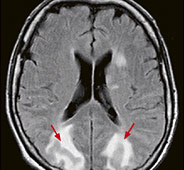

Abb. 3

Kopfschmerzen und Sehstörungen bei krisenhafter Blutdruckerhöhung. Die Signalveränderungen der MRI-Untersuchung zeigen die charakteristischen, reversiblen Wassereinlagerungen in beiden Hinterhauptslappen (Pfeile).

Die Magnetresonanztomographie ist bei der Kopfschmerzabklärung das Verfahren der Wahl, weil es auch subtile Hirnstrukturen kontrastreich abbildet. Hirnhäute und Hirnnerven, die bei der Kopfschmerzentstehung eine Rolle spielen können, sind beispielsweise mittels CT nicht hinreichend beurteilbar. Haben Patienten neurologische Begleiterscheinungen, wie Kraftschwäche, Sensibilitätsstörungen, Sehstörungen oder Bewusstseinsveränderungen, ist das MRI in jedem Fall zu bevorzugen.